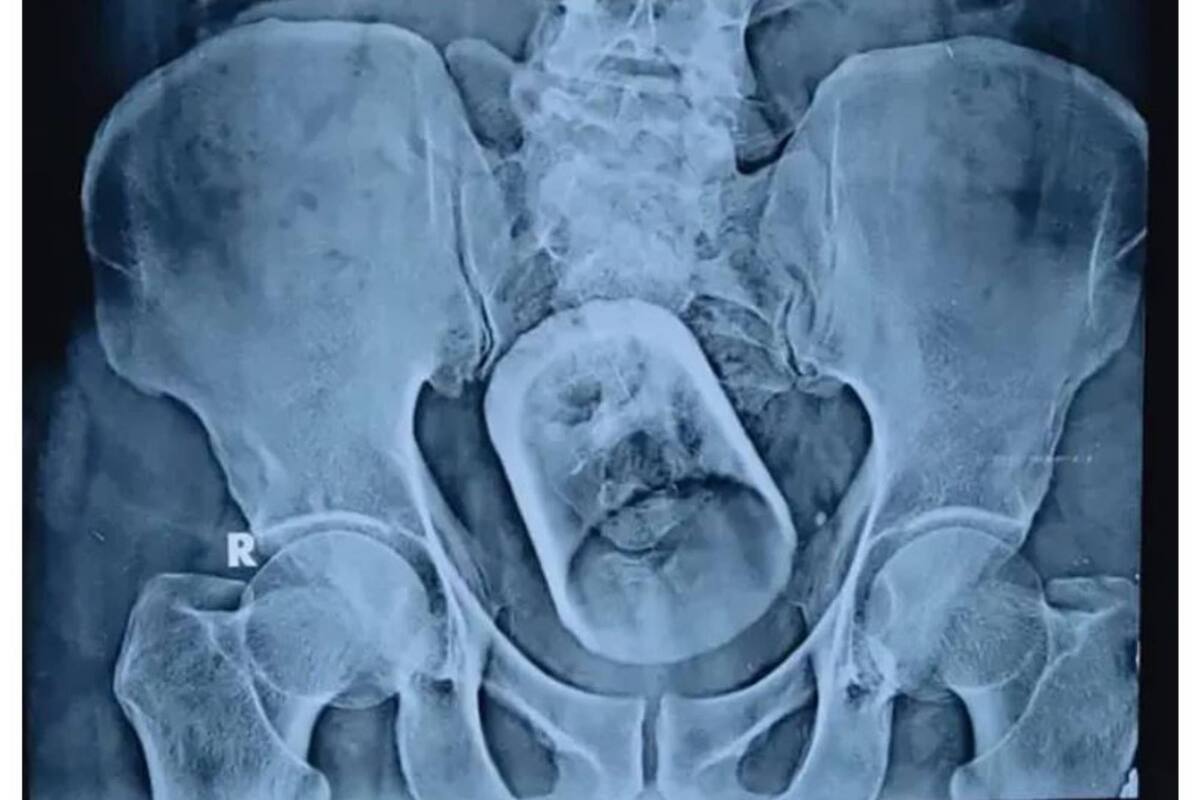

En un hospital de Bihar, India, un paciente llegó esta semana con estreñimiento y un fuerte dolor abdominal. A la hora de indagar en los motivos de su dolencia, los médicos decidieron hacerle una radiografía que arrojó un resultado sorprendente.

Resulta que esta persona de 55 años tenía en su estómago un vaso que se había tragado accidentalmente mientras tomaba té, lo cual le generó una “perturbación grave” en sus intestinos. El siguiente paso fue resolver cómo extraerían el objeto. Primero, intentaron hacerlo a través del tradicional método endoscópico. Sin embargo, los doctores no lograron extirpar el vaso, por lo que tuvieron que pasar a la segunda alternativa: una intervención quirúrgica.

Los profesionales dudaron de que el paciente se hubiera tragado el vaso “accidentalmente”, puesto que el tamaño del objeto insertado es demasiado grande para que pueda pasar por el tubo de alimentación humano. “Cómo entró en el cuerpo del paciente sigue siendo un misterio”, dijo Mahmudal Hasan, jefe del equipo médico a cargo de la cirugía. Tras la operación, el paciente se recuperaba sin mayores complicaciones. Afortunadamente, se encuentra actualmente estable después de su curioso percance.